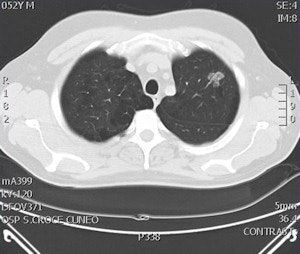

Digital tomosynthesis detected a left apical nodule in a 52-year-old male smoker. All images courtesy of Stephane Chauvie, PhD, and Dr. Maurizio Grosso.

Digital tomosynthesis detected a left apical nodule in a 52-year-old male smoker. All images courtesy of Stephane Chauvie, PhD, and Dr. Maurizio Grosso. CT confirmed the nodule in the patient and consequently he underwent surgery, which confirmed the tumoral nature of the nodule.

CT confirmed the nodule in the patient and consequently he underwent surgery, which confirmed the tumoral nature of the nodule."We have very preliminary data, but we believe digital tomosynthesis is a quite good method of detection for nodules," Grosso said.